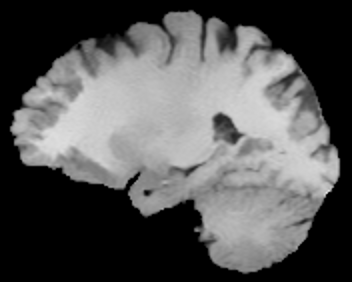

VII-C Experiments with real-life data

Reconstruction of real-life MRI images has been the next step in our comparative study. To this end, the data set of [19] have been used herein. The data were obtained at the University Hospital of Ghent and it is publicly available at http://telin.ugent.be/~sanja/Sanja_files/Software/MRIprogram.zip. The data contains a sagittal and an axial scan of a human brain, which are shown in Fig. 10 and Fig. 11, respectively.

The reconstruction results obtained for each of the tested images using the proposed and reference methods are shown in Subplots (b)-(f) of Fig. 10 and Fig. 11, respectively. From these figures, it can be seen that the proposed algorithms result in higher-contrast reconstructions of better visual clarity as compared to the reference approaches. The difference is particularly evident for the case of Fig. 11, where the proposed algorithms result in less noisy images, while exhibiting higher effective resolution and contrast.

Figure 10: (a) Sagittal MRI scan; (b)-(f) Reconstruction results obtained using TVDN, WDN, GNLM, NLMS and NLMR, respectively.